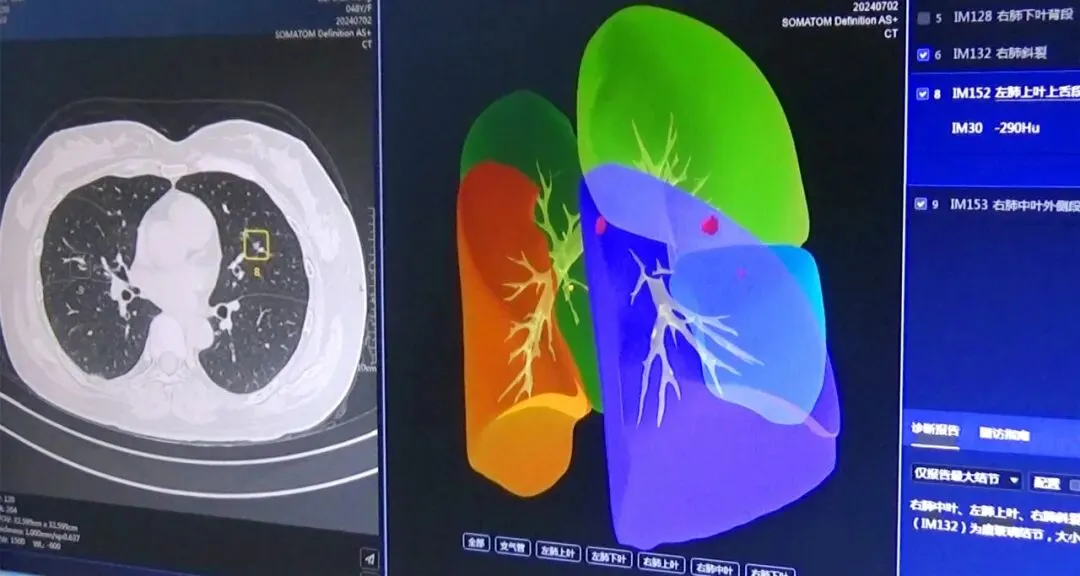

为提高医学影像的精准诊断率,我院引进了人工智能(AI)影像辅助诊断系统——肺结节智能分析系统。

肺结节AI自动检测及量化分析:AI系统可避免肺小结节的漏诊,尤其可以大幅度降低血管旁、微小结节、淡磨玻璃结节漏诊概率,大大提高肺小结节的检出率,结合AI自动量化分析参数,有效提升肺小结节精准诊断。

肺结节AI智能随访,建立随访档案,客观准确量化肺结节随访:针对同一患者的多次影像检查,AI自动精准匹配病灶,并提供该病灶变化的多种定量参数,包括病灶大小、体积变化率、病灶类型、病灶新增或消失评估、倍增时间计算等,并且生成关于该病灶的体积变化、密度变化的趋势图,直观辅助精准随访评估,辅助肺结节治疗的预后及疗效评估。